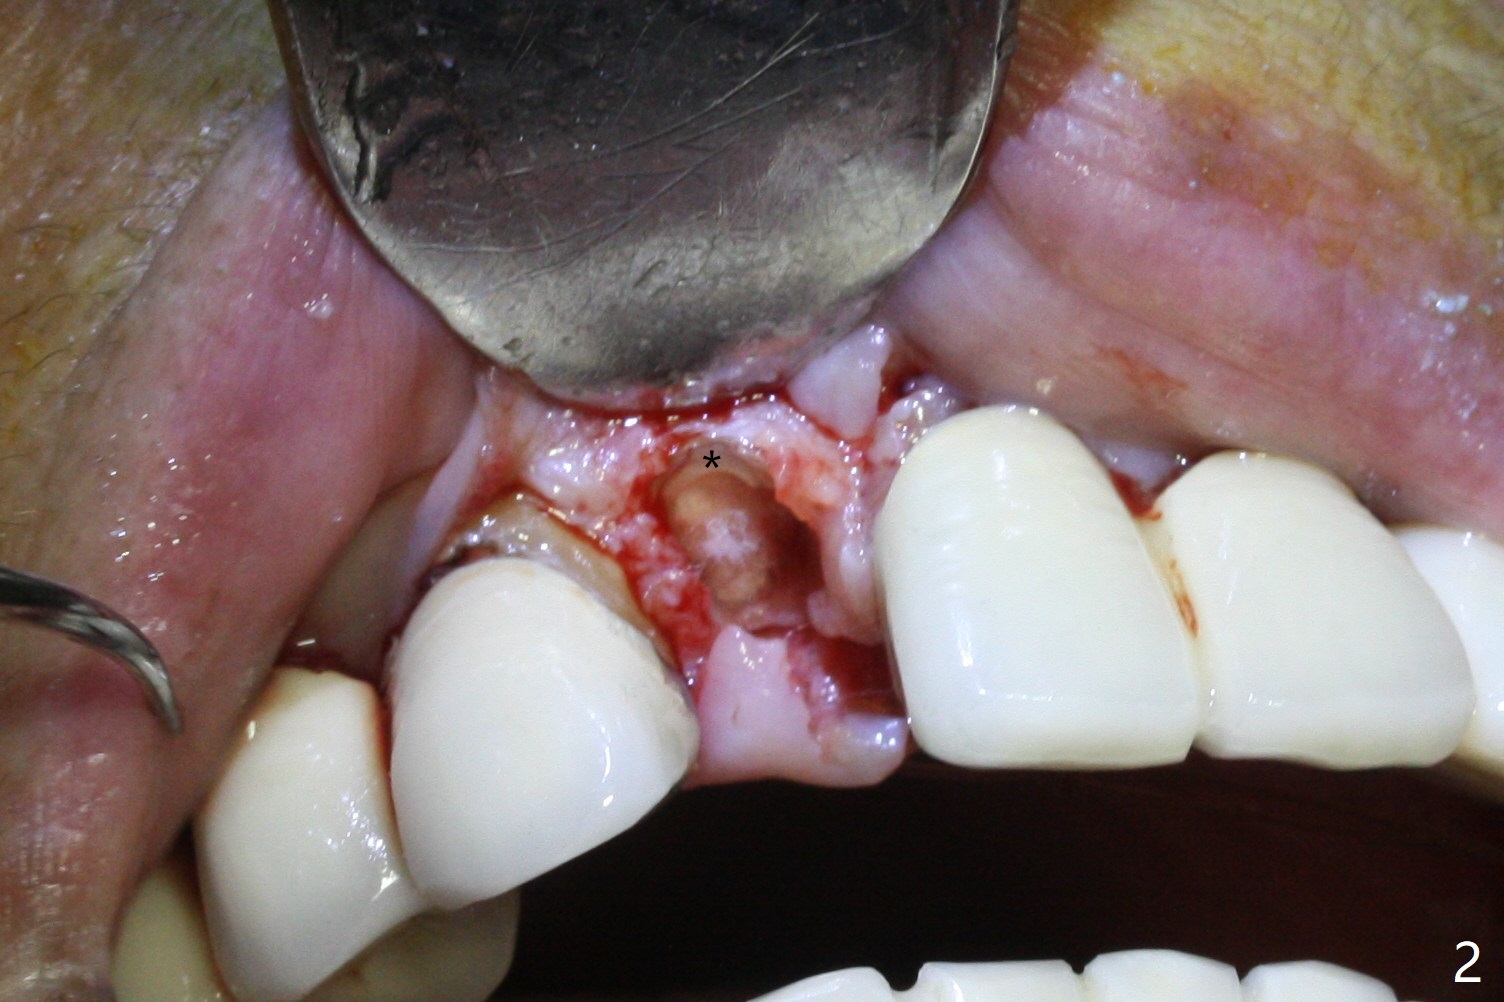

The edentulous area at #7 is narrow both buccopalatally and mesiodistally, whereas the crowns of the neighboring teeth are long (Fig.1,2). For the latter reason, it is difficult to remove the apical portion of the root, including gutta percha with surgical handpiece (Fig.3 *) for socket shield (Fig.2 *). To avoid the perspective implant touching socket shield, initial osteotomy is palatal. When a 2 mm drill is being used, the coronal end of the palatal plate starts to perforate. A 2.5x14 mm 1-piece implant is placed with 30 Ncm (Fig.4). The palatal plate is thin (Fig.5). Preop CT will help determine the position of initial osteotomy. The buccal gingiva seems to have been re-attached to the underlying alveolus and the provisional 1 month postop (Fig.6). The teeth #8 and 9 fracture (an implant is placed at #8 and bone graft at #9, while the implant at #7 is osteointegrating (Fig.7). In fact the shield is exposed without symptom. A year postop, another dental provider sends a photo of apparently hemorrhagic gingiva around #7 crown (Fig.8). A few days later with oral hygiene instruction, the gingiva around the exposed root piece is healthy (Fig.9). The root surface is reduced; with socket shield, there is no buccal plate collapse; in contrast the neighboring buccal plate (at #8 and 9) is concave (Fig.10). There is minimal exposure 11 days postop (Fig.11). The gingiva palatal to the shield is erythematous, a possible sign of periimplantitis. The socket shield at #7 appears to be fused with the buccal plate 11 months postop (Fig.12), as compared to the implant at #10 nearly 4 years postop (Fig.14). The buccopalatal widths at #7 and 10 are equivalent (Fig.13,15).